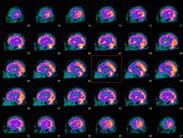

PET-CT検査